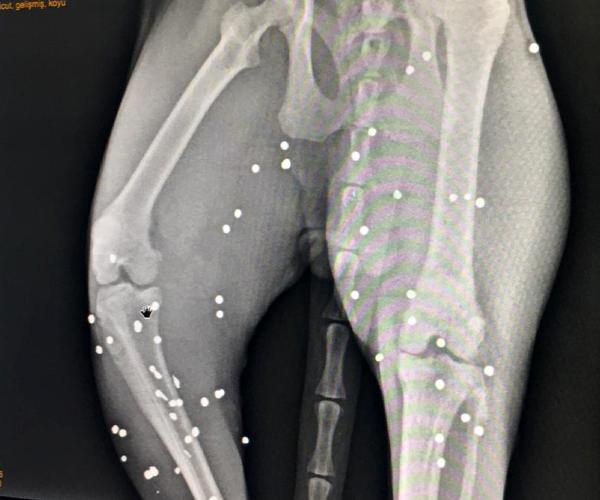

Veteriner Atila Sargın tarafından filmleri çekilen kedinin arka ayaklarının olduğu bölgede çok sayıda saçma izine rastlandı. Yürümekte zorlanan ve arka ayaklarının üzerine güçlükle basan kedinin tedavisine başlanırken, Manavgat İlçe Jandarma Komutanlığı’nca olayla ilgili inceleme başlatıldı.

Veteriner hekim Atila Sargın da Şenay Yılmaz'ın kendisini aramasından sonra olaydan haberdar olduğunu belirterek, “Gelip baktığımda kedinin durumunun kötü olduğunu gördüm. Hemen aldım kliniğe götürdüm. Röntgeni çekince gördüm ki kedinin arka tarafında çok sayıda saçma var. Yani kedinin arka tarafında tüfekle ateş edilmiş. Bu kedi teyzenin canı gibi. Bir yıldır tanıyorum teyzeyi. Sürekli gelip kediye bakardım, onun aşılarını filan yaptım. Şu an kedinin tedavisine devam ediyoruz” diye konuştu.

'80 TANE SAÇMA VAR'

Hayvanlara yönelik şiddete son verilmesi gerektiğini belirten Sargın, sözlerini şöyle sürdürdü: “Bu canlarımıza artık böyle insanlar silah sıkmazsa, kurşun sıkmazsa çok mutlu olacağız. Kedinin vücudunda çok miktarda saçma var, belki 70- 80 tane. Bunu tek tek ameliyatla toplama şansımız yok. Bunu kedi enfeksiyon kapmadan bir şekilde düzelteceğiz. Zaten 2 gün öncesine göre şu an biraz daha iyi."

Deri altında olan saçmaların operasyonla alınacağı, derinde olanların ise alınması durumunda hayvanın daha fazla zarar göreceği için çıkarılmayacağı ve ilaç tedavisiyle zarar vermeyecek hale getirileceği öğrenildi.